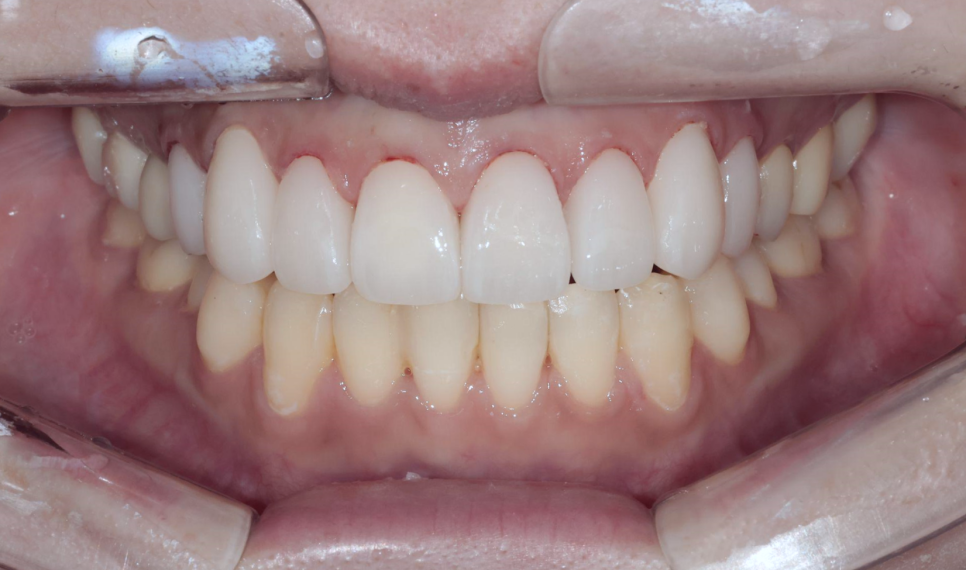

시술 결과 - 보철물 부착 후

8개 앞니에 올세라믹 크라운을 부착한 후의 결과를 보여드리겠습니다.

8전치 올세라믹 크라운 부착 직후

부착 직후 사진을 보시면, 잇몸과 보철물의 경계가 자연스럽게 이어지고 주변 잇몸 상태도 안정적인 것을 확인할 수 있습니다. 절단면이 균일하고 가지런하게 정리되었고, 이전에 돌출되어 있던 오른쪽 위 송곳니도 자연스러운 치열 배열을 이루게 되었습니다.

무엇보다 환자분의 스마일 라인이 확실히 개선되었습니다. 웃을 때 치열이 가지런하고 자연스러운 곡선을 이루면서, 전체적인 인상이 훨씬 깔끔하고 밝아지셨습니다.

Before & After 비교 요약

치료 전후를 한눈에 비교해 볼게요.

이 케이스에서 가장 의미 있는 점은 심미적 개선과 치아 보존이라는 두 가지 목표를 동시에 달성했다는 것입니다. 환자분은 예쁜 앞니를 원하셨고, 저는 거기에 더해서 위산으로부터 치아를 보호하는 것까지 해결해 드릴 수 있었습니다. 신경치료 없이 생활치 상태를 유지한 것도 치아의 장기적인 건강을 위해 매우 긍정적인 결과였다고 할 수 있습니다.